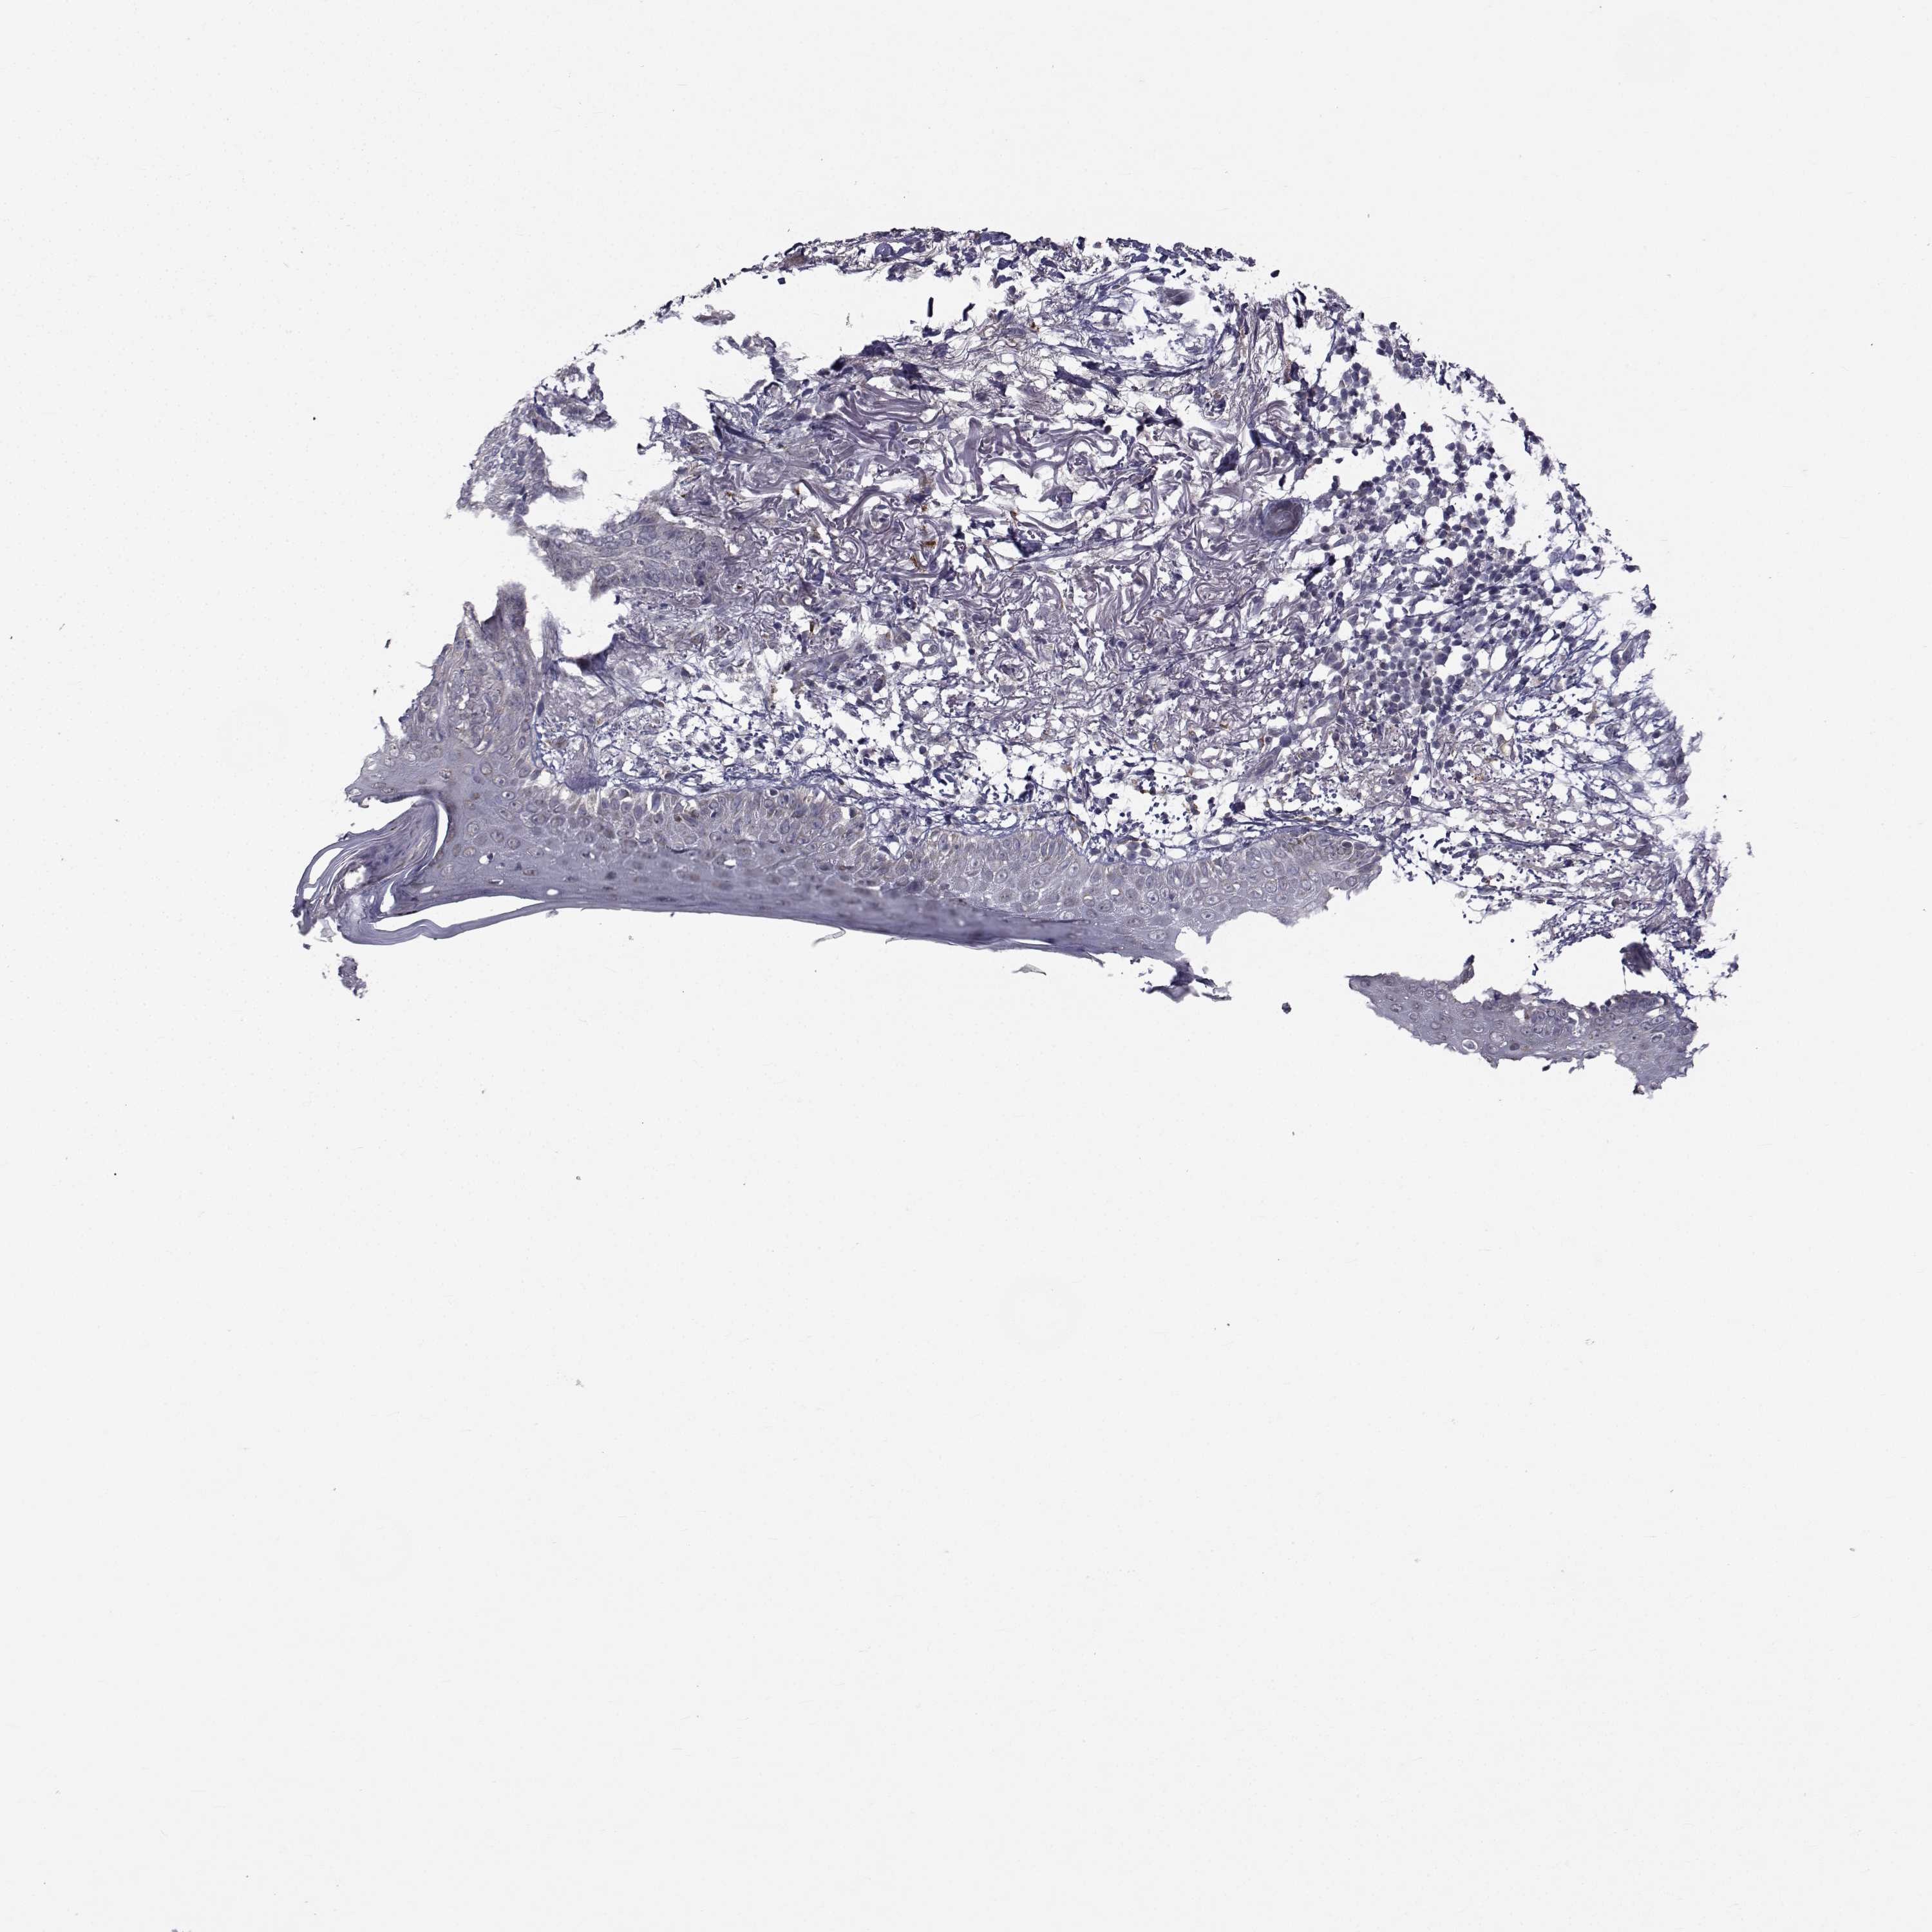

SKIN CANCER - Protein expressioni

A mouse-over function shows sample information and annotation data. Click on an image to view it in a full screen mode. Samples can be filtered based on level of antibody staining by selecting one or several of the following categories: high, medium, low and not detected. The assay and annotation is described here.

Each image is clickable and will lead to virtual microscopy that enables deeper exploration of all samples and also displays staining intensity scores, fraction scores and subcellular localization as well as patient and tissue information for each sample.

Antibody HPA044393

Antibody HPA053673

Antibody CAB009818

Staining

High

Medium

Low

Not detected

Intensity

Strong

Moderate

Weak

Negative

Quantity

>75%

75%-25%

<25%

None

Location

Nuclear

Cytoplasmic/membranous

Cytoplasmic/membranous,nuclear

Squamous cell carcinoma, NOS

Basal cell carcinoma